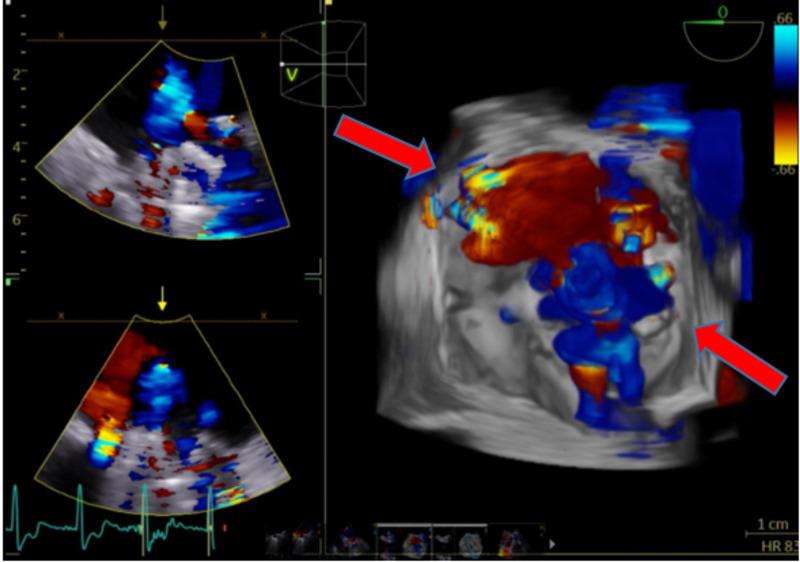

二尖瓣置换术后瓣周漏的复杂病例

A Complicated Case of a Paravalvular Leak Following Mitral Valve Replacement.

Paravalvular leaks (PVL) are an uncommon sequelae of valve replacement but can be seen as a complication of both mechanic and prosthetic valves. Patients with PVL may remain asymptomatic or have detrimental complications, which include heart failure, hemodynamically significant hemolysis, and endocarditis. Management depends on the clinical presentation and the degree of the valvular leak. We hereby present a case report of a patient with a complicated clinical course secondary to a PVL of the mitral valve. The patient had a recent mitral valve replacement and presented with symptoms of heart failure that was refractory to standard medical therapy. Valvular abnormality was not seen with initial trans-thoracic echocardiogram (TTE), but with high clinical suspicion, a trans-esophageal echocardiogram (TEE) was done confirming a PVL. The patient's condition continued to deteriorate; he became hemodynamically unstable with end-organ damage. Cardiothoracic surgery was consulted for surgical repair of the PVL. The patient, however, remained too unstable for surgery and the family opted for comfort measures per the patient's wishes.

摘要

瓣周漏(PVL)是瓣膜置换术后不常见的后遗症,但可视为机械瓣膜和人工瓣膜的并发症。瓣周漏患者可能无症状或出现有害并发症,包括心力衰竭、具有血流动力学意义的溶血和心内膜炎。治疗取决于临床表现和瓣膜漏的程度。我们在此报告一例二尖瓣瓣周漏继发复杂临床过程的病例。该患者近期进行了二尖瓣置换术,出现了标准药物治疗无效的心力衰竭症状。最初的经胸超声心动图(TTE)未发现瓣膜异常,但由于临床高度怀疑,进行了经食管超声心动图(TEE)检查,证实存在瓣周漏。患者病情持续恶化;他出现血流动力学不稳定并伴有终末器官损害。咨询心胸外科进行瓣周漏的手术修复。然而,患者仍因过于不稳定而无法进行手术,家属根据患者意愿选择了姑息治疗措施。